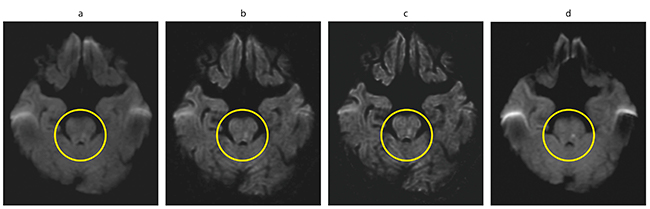

cDWIを用いた症例を提示する。79歳,女性,症状はろれつが回らない,嘔吐である。実測のDWI(以下,aDWI)b=1000s/mm2とcDWI b=2000s/mm2,cDWI b=3000s/mm2,翌日にフォローアップしたaDWIを比較した(図3)。cDWI b=2000s/mm2,cDWI b=3000s/mm2を作成することで梗塞巣が明瞭になった。このように,梗塞巣が明確でなく,梗塞疑いの診断を受けた14例中11件でフォローアップの梗塞巣と一致し,cDWIによる診断能向上が確認できた。

図3 症例でのaDWIとcDWIの比較

a:aDWI=1000s/mm2

b:cDWI=2000s/mm2

c:cDWI=3000s/mm2

d:翌日 aDWI=1000s/mm2